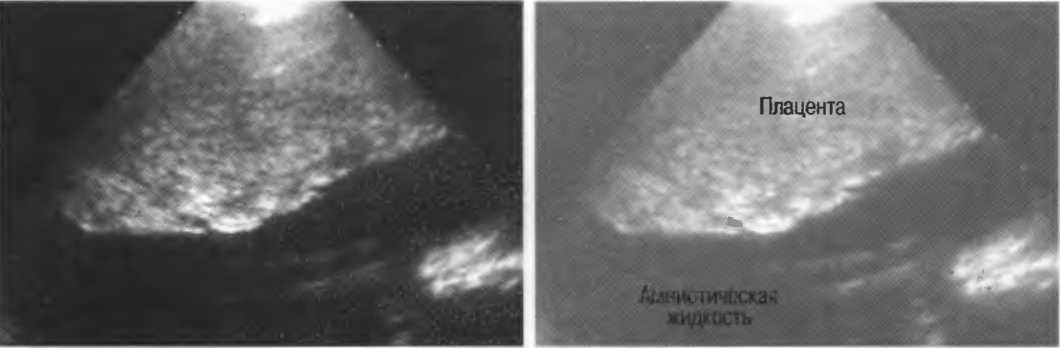

Рис. 10б. При исследовании печени и асцитической жидкости через межреберные промежутки ребра дают две тени, а в асцитической жидкости определяются реверберации.

Рис. 10в. Исследование того же пациента под углом через межреберный промежуток, при этом тень от ребер и реверберации не визуализируется.